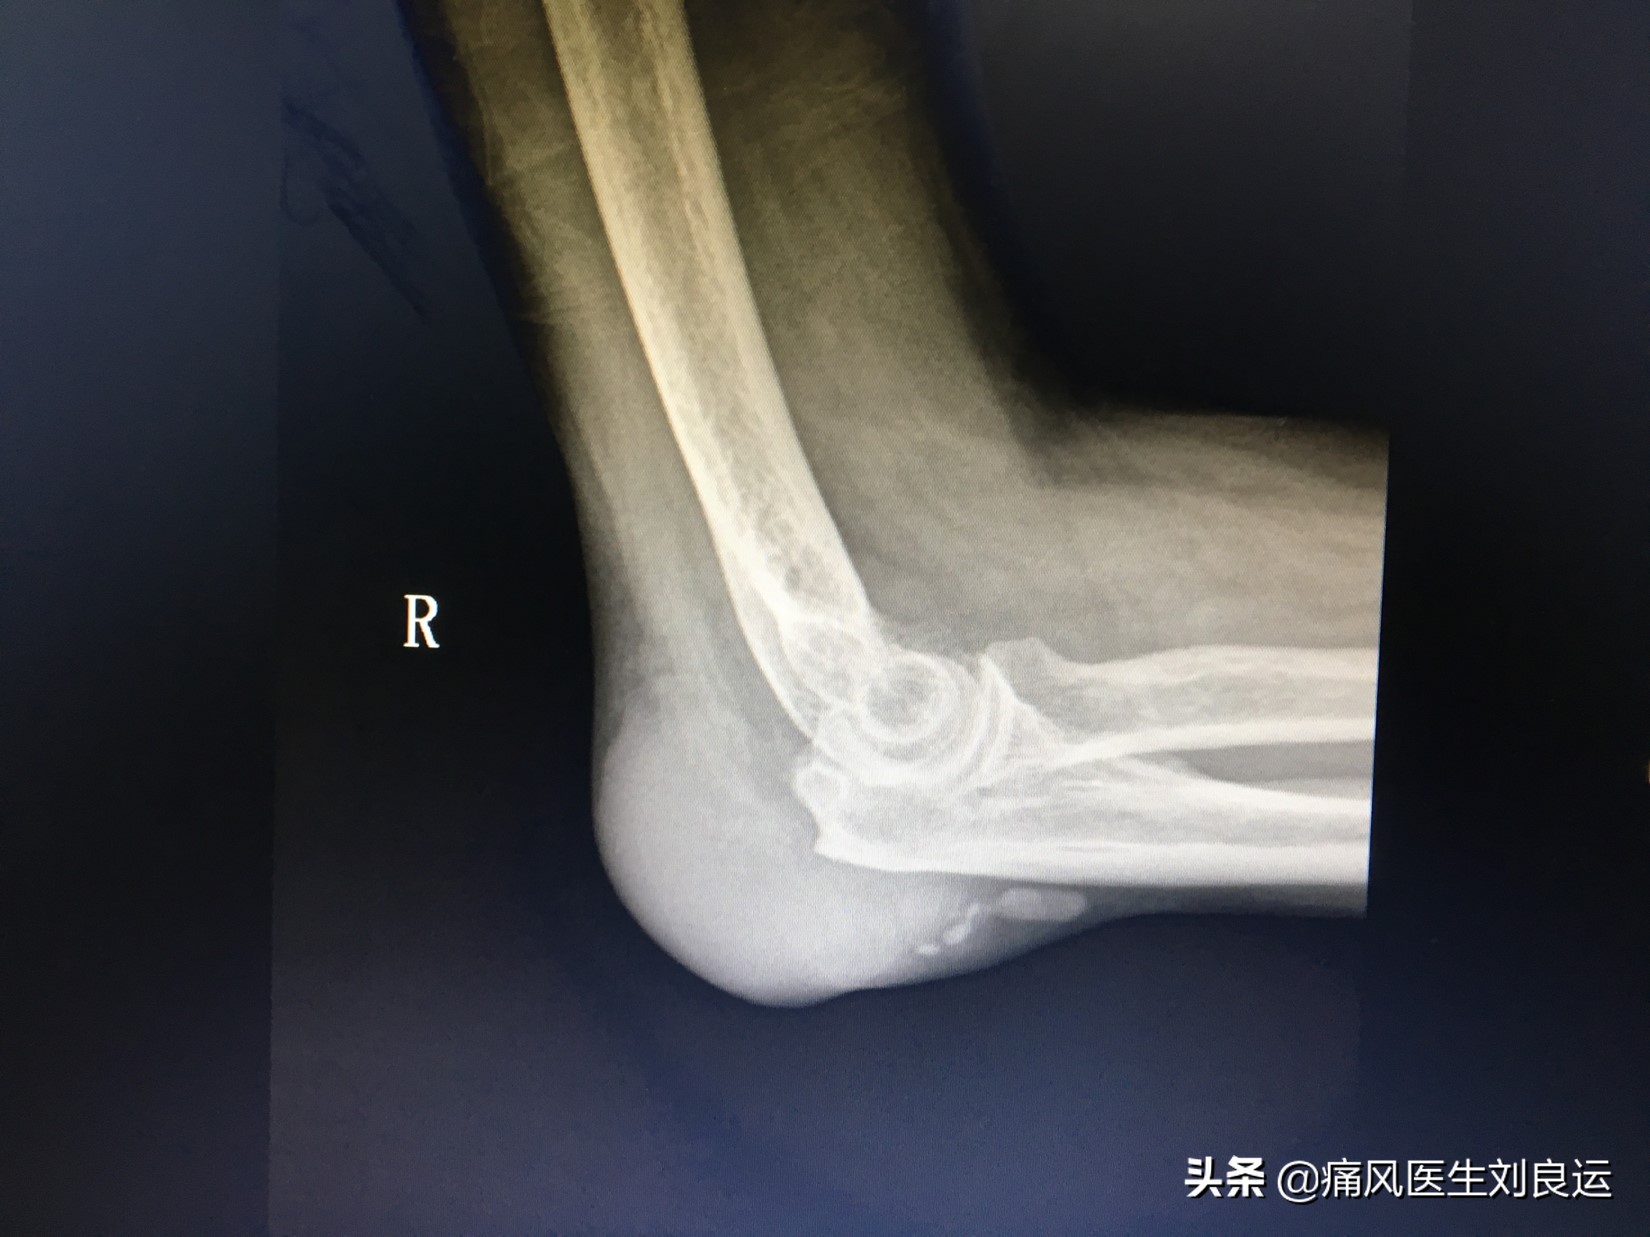

X线下肘关节痛风石

- 好发于外耳的耳轮、尺骨鹰嘴、指间和掌指关节、指端皮肤、手掌、腕关节、跖趾、踝关节、足背、足底、膝关节等处;

随着痛风病情进展,往往会引起大小不一的痛风石的发生。痛风石的出现,意味着痛风病程已经进入了第四阶段,疾病已经越发严重了,如果继续放任痛风发展,痛风就要开始“攻占”*体器人官**了。痛风石可分布于全身各部位,早期无明显症状,随着疾病的发展可出现局部破溃甚至坏死,少有继发感染,位于骨骼关节的痛风石可引起骨骼关节的破坏,严重时可导致畸形、截肢。